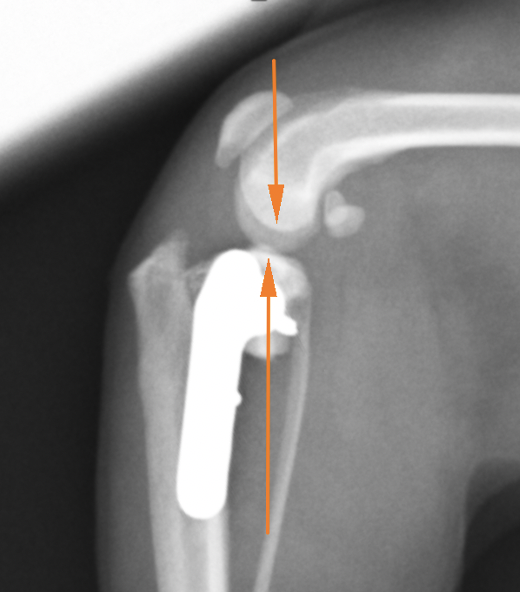

術後のレントゲン画像です。先程までずれていた矢印が合っているのがわかります。

またTPAと呼ばれる角度も小さくなっているのが確認できます(6°)。6°前後が理想的と言われています。